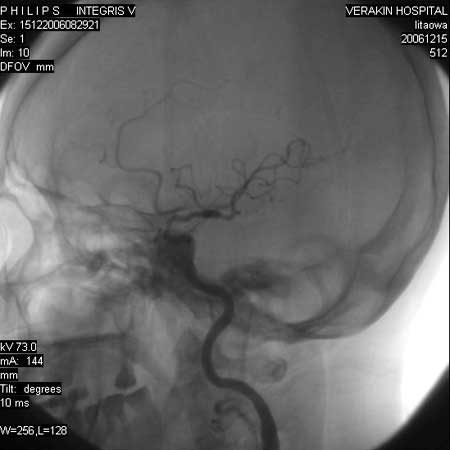

标题: DSA0063:颈内动脉血管造影

女,60岁,行全脑血管造影,图片较多,选了左颈内动脉造影100幅图中的10幅图片,请包涵。

支持后交通动脉起始部动脉瘤。

后交通动脉瘤.

另外:大家讨论的\"动脉瘤\"实际是血管分支重叠影像,本帖单侧颈内动脉仅见轻度动脉硬化性狭窄..参考旋转dsa请连接:http://www.sdhct.com.cn/radinet/read.php?tid=19818